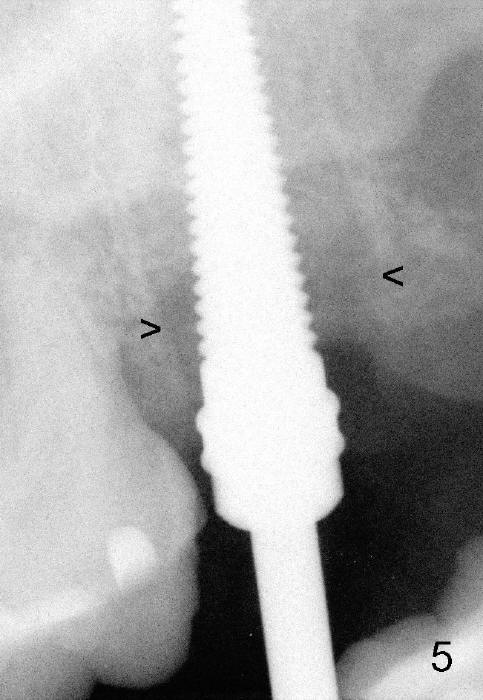

A 57-year-old lady presents for abscess buccal to the tooth #15 (Fig.1 A). Mesial and distal to the occlusal composite (Fig.2 C) is a crack line. In addition to long furcated roots, the upper border of the bone is not shown in this preop PA (arrow). Fig.3 is taken to show a thin septum surrounded by the mesiobuccal (MB), distobuccal (DB) and palatal (P) sockets (Fig.3). Osteotomy is initiated in the septum by 1.2 and 1.5 mm pilot drills, followed by 2,3,4 mm rounded tapered osteotomy at the depth of 17 mm. Nose blowing test is carried out after each step with negative result. Stability is achieved when a 4.5 mm tap is inserted at 17 mm, but the upper end of the tap is not visible (Fig.4,5). When a 5 mm tap is placed, stability is decreased, probably because the coronal end of the septum starts to break down (due to expansion). To re-gain stability, the 5 mm tap needs to go deeper. A 6 mm tap also achieves satisfactory stability at 20 mm. When the tap is removed, there is no air leakage. A 6x20 mm implant is placed with insertion torque > 60 Ncm; the upper end of the implant is still out of view in PA (Fig.6). Another problem is that the implant needs to go deeper to obtain sufficient occlusal clearance. The lower first molars and the 2nd premolars are missing. A panoramic X-ray has to be taken to show the apical end of the implant: ~ 3 mm into the sinus (Fig.7 ^). The maxillary tuberosity appears to grow downward (arrow). In other word, the tooth #15 appears to have been intruded due to overloading.